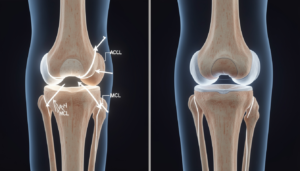

Uszkodzenia więzadeł kolana (ACL, MCL)

Zerwałeś więzadła w kolanie? ACL czy MCL – czym się różnią i co dalej?

Kontuzja więzadeł stawu kolanowego to jeden z najczęstszych urazów u osób aktywnych. Dwie najbardziej narażone struktury to ACL